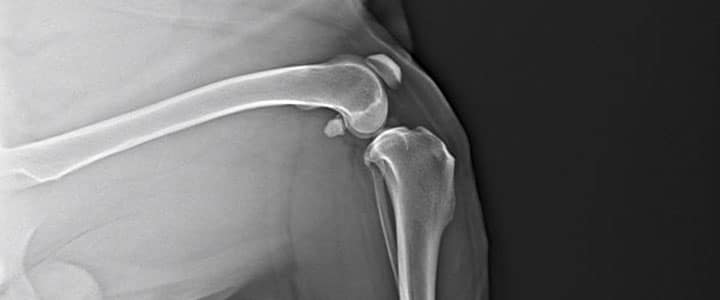

Digital Radiology (X-rays)

Providing clear images of bones, organs, and soft tissues to diagnose fractures, respiratory problems, gastrointestinal issues, and more.